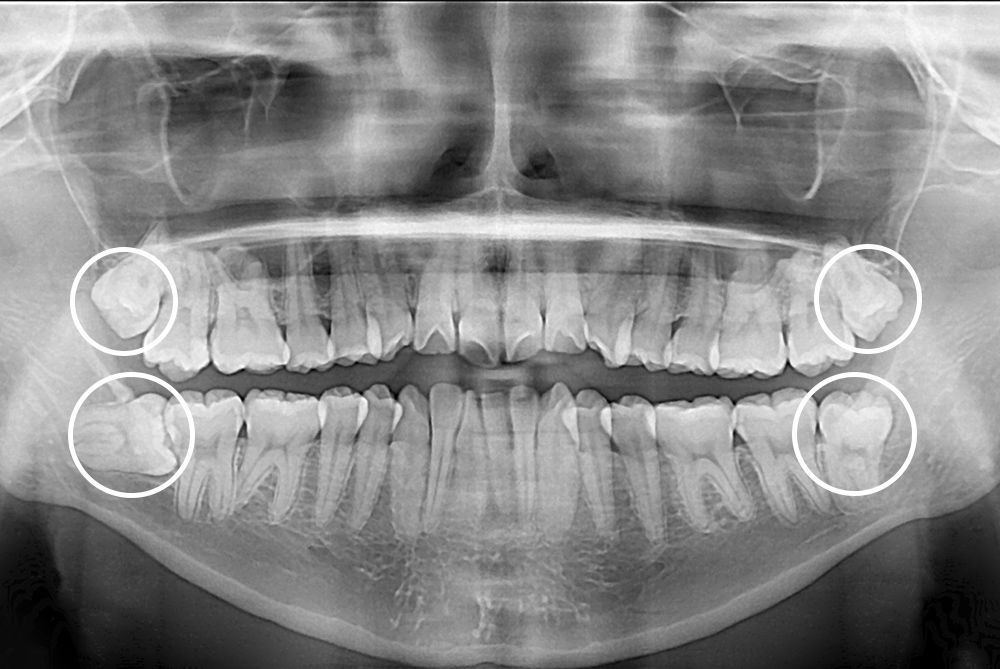

[사랑니] 매복 사랑니 발치

치료후 : 2019-06-20

세종치과는 구강악안면외과학 박사이신 원장님이 발치하는 치과입니다.